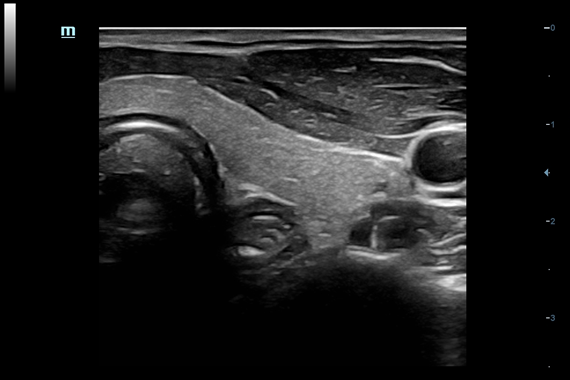

DC-60 EXP X-INSIGHT - это современный стационарный УЗИ-аппарат с функцией сенсорного управления и очищенной гармонической визуализацией, обеспечивающей лучшее контрастное разрешение и технологию 4D-визуализации. Он оснащен 21,5-дюймовым монитором, который может поворачиваться на 180 градусов, что удовлетворяет потребности врачей в качественной ультразвуковой диагностике.

• PSH™ - технология гармонической визуализации с фазовой инверсией.

• iBeam™ - режим многолучевого компаундинга.

• iClear™ - адаптивный режим шумоподавления.

• PSH™ - гармоника с фазовой инверсией

• iBeam™ - режим многолучевого компаундинга

• iClear™ - адаптивный режим шумоподавления